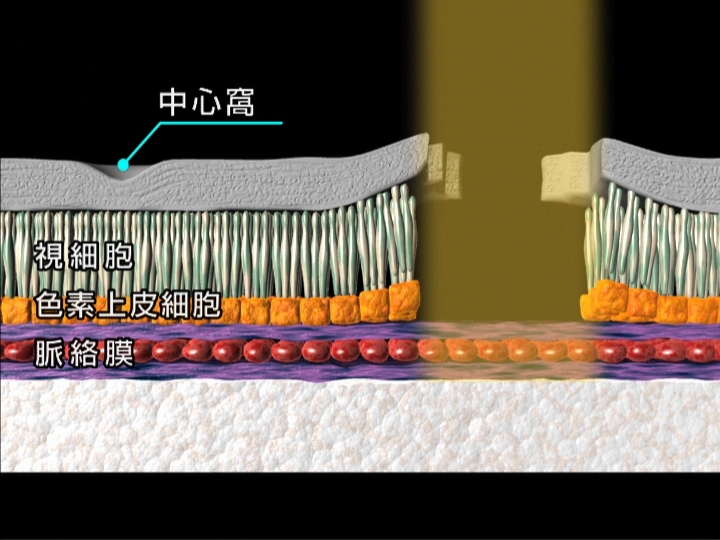

網膜剥離の場合には、視野欠損が生じます。視野の一部が見えなくなります。網膜剥離を放置して、網膜の中心部分(黄斑部)が剥がれると、視力が大幅に低下します。また眼鏡やコンタクトレンズを使っても矯正はできません。症状に気づいた時には、すぐにご相談ください。

網膜剥離の場合には、視野欠損が生じます。視野の一部が見えなくなります。網膜剥離を放置して、網膜の中心部分(黄斑部)が剥がれると、視力が大幅に低下します。また眼鏡やコンタクトレンズを使っても矯正はできません。症状に気づいた時には、すぐにご相談ください。